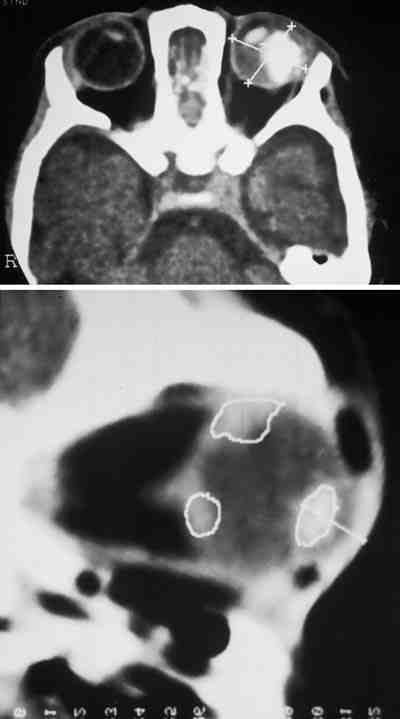

25-04.jpg (36066 bytes)

Figuras 4a, b, c y d. Retinoblastoma en ojo derecho.

Secuencias potenciadas en T1 tras la administración de gadolínio (a) y potenciada en T2 (b). RM de control 17 meses tras finalizar el tratamiento (c, d).

Ausencia de captación tumoral de gadolínio (c) así como reducción del componente cálcico (d) respecto a estudio basal potenciado en T2 (b).